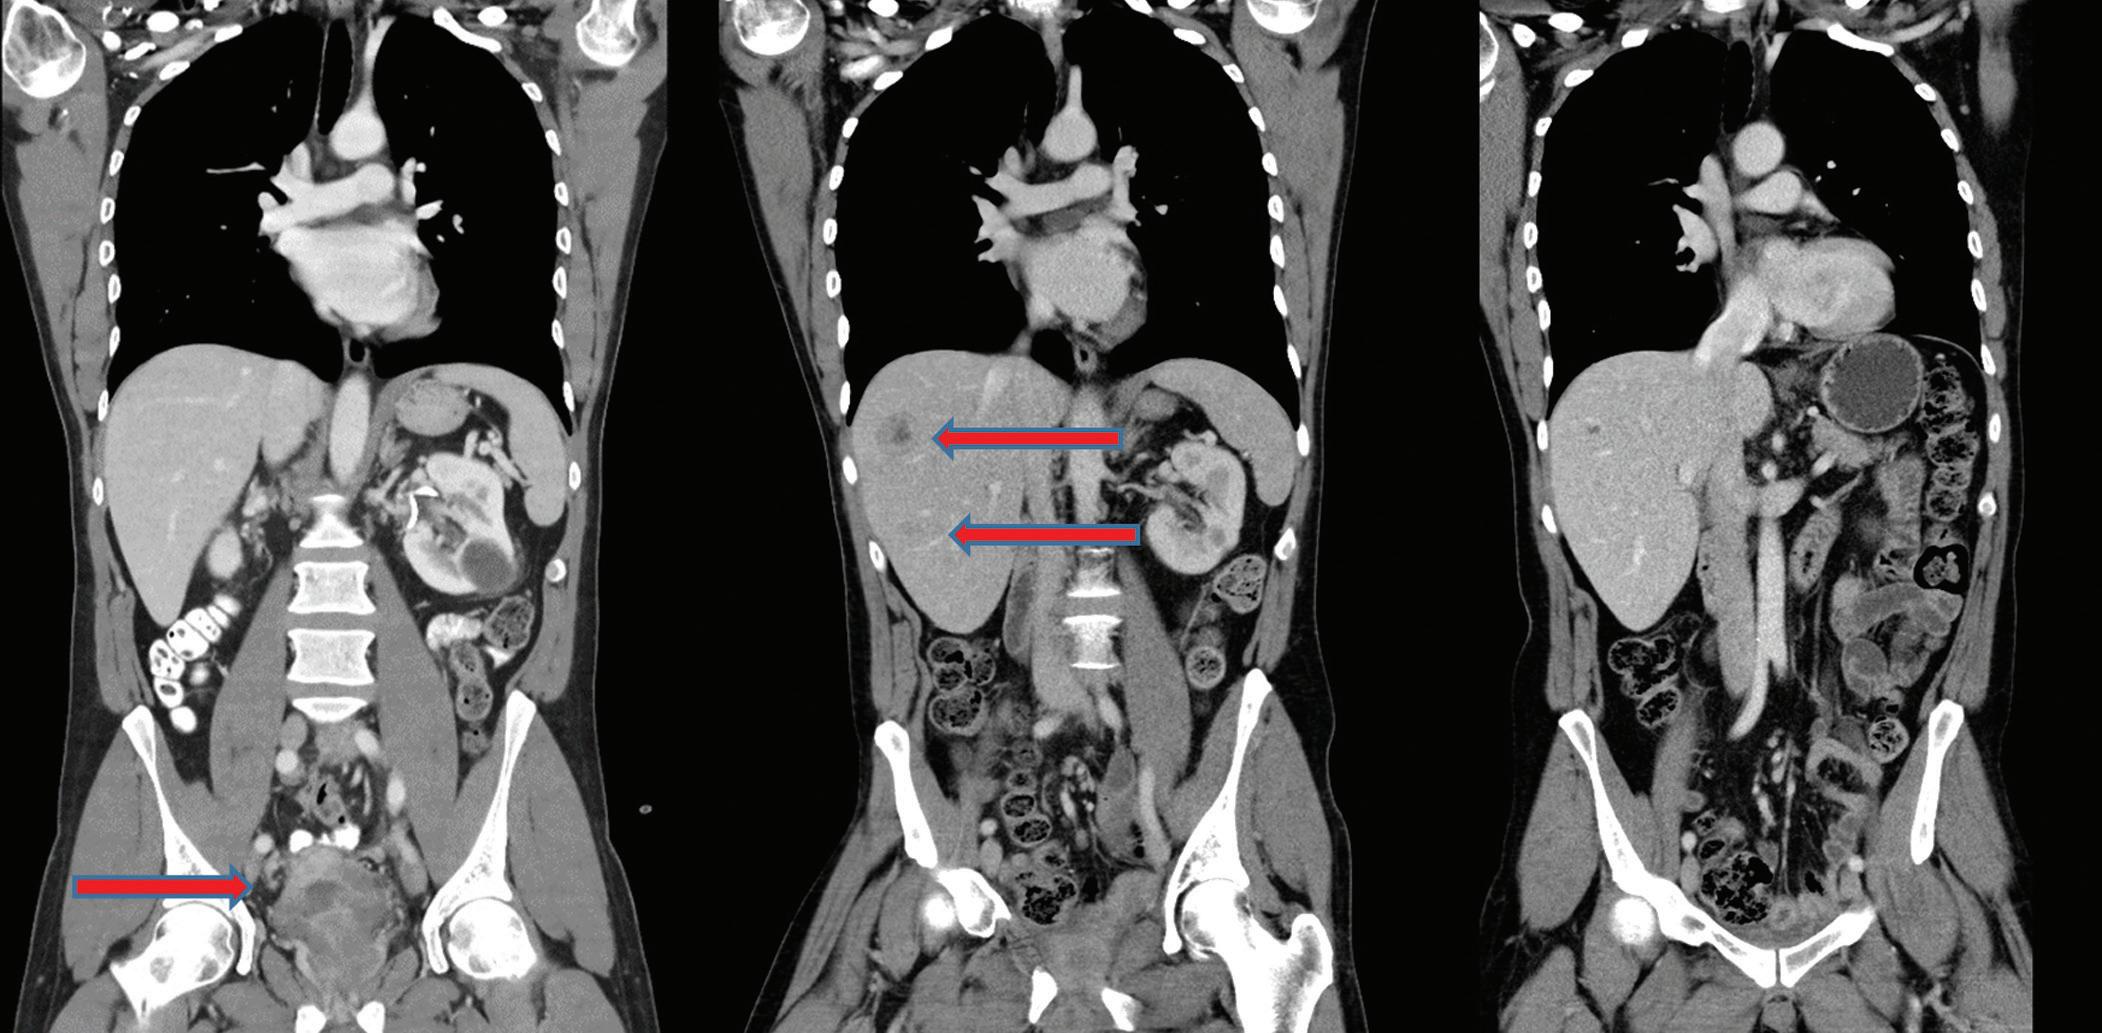

Václav Krejčí1, Miloš Broďák1, Antonín Krajina1,2, Jaroslav Pacovský1

1 urologická klinika lf uK a fn hradec Králové

2 radiodiagnostická klinika lf uK a fn hradec Králové

MUDr. Václav Krejčí urologická klinika lf uK a fn hradec Králové sokolská 581

500 05 hradec Králové vaclav.krejci1@fnhk.cz

doručeno: 28. 6. 2024

Přijato: 12. 12. 2024

anatomického uspořádání okolních orgánů. Další možností je provést kombinovaný výkon transplantace ledviny společně s ipsilaterální nefrektom ií ledviny nativní v jedné době. Všechny postupy mají své výhody i nevýhody. Kombinovaný výkon je spojen s menší kumulativní délkou výkonu a nižším rizikem potřeby krevních transfuzí. Je zároveň třeba větší incize a operační pole, což může komplikovat hojení při nezbytném podávání imunosupresivní léčby [1]. Mimo to mají obvykle pacienti s polycystózou ledvin opakované infekce nebo krvácení do jednotlivých cyst [2,3]. U závažných nebo často recidivujících případů to také může být důvodem pro odstranění nativních ledvin ještě před transplantací.

Obr. 1. Preparát polycystické ledviny.

Fig. 1. Polycystic kidney specimen.

Obr. 2. Polycystické ledviny a ledvinový graft v pravé jámě kyčelní.

Fig. 2. Polycystic kidney and renal graft in the right iliac fossa.